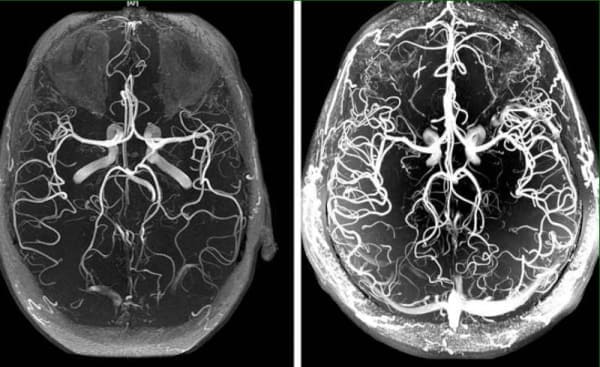

Keringési zavarok az agyban - hogyan ismerjük fel a közelgő katasztrófát, és hogyan védekezzünk a veszélyes következmények ellen.

Az agyi keringési zavar egy olyan állapot, amelyben az agyszövet érrendszeri tónusa és normális véráramlása zavart szenved. Ebben a cikkben olvashat az okokról, mechanizmusokról és jelekről, amelyek esetén ideje riadót fújni. Olvashat ennek az alattomos állapotnak a súlyos szövődményeiről és a leküzdésére alkalmas, mindenki számára elérhető, modern megközelítésekről is.

Az agyi vérkeringés károsodása kihat az egész test teljesítményére. Az agy elégtelen vérellátása miatt csökken az általános teljesítmény, gyengeség lép fel, és fontos testrendszerek kezdenek rosszul működni.